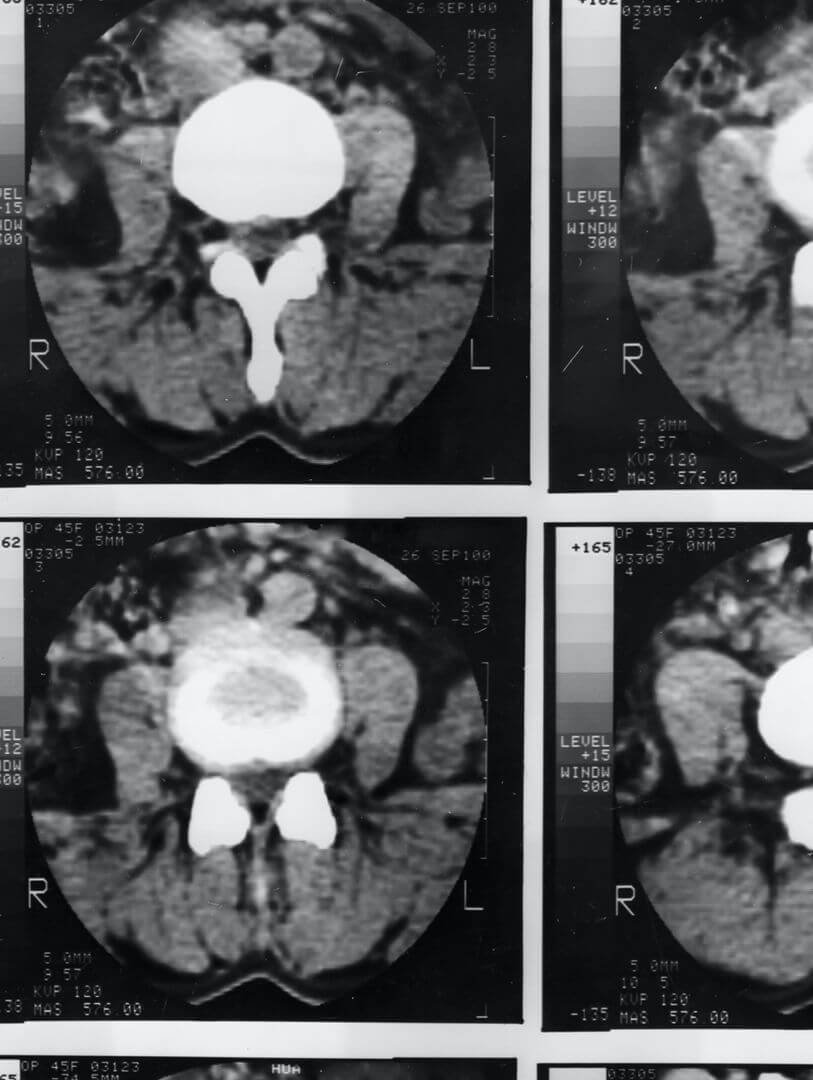

Le juge s’appuie le plus souvent sur une expertise médicale. Cette expertise permet de déterminer les seules conséquences de l’aggravation. C’est pourquoi, les missions d’expertise en aggravation sont très spécifiques car le médecin-expert doit précisément décrire le préjudice antérieur à l’aggravation pour comparer avec ses nouvelles constatations et fixer une nouvelle date de consolidation pour permettre une éventuelle demande nouvelle en aggravation.